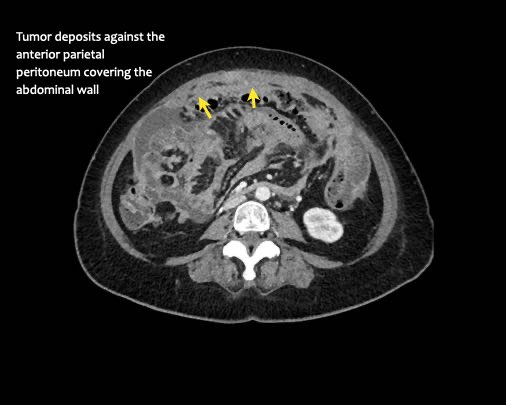

Ca lâm sàng 2

Cuộn qua các lát cắt.

Bạn có thể phát hiện tất cả các tổn thương cấy ghép phúc mạc không?